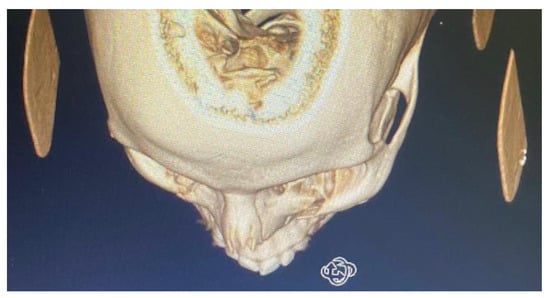

By counting the occurrence of the sites of fracture, either alone or combined, we found that the orbital floor (n = 52, 41.9%; Figure 1) and lateral wall (n = 31, 25.0%) were the most prevalent sites of bone fracture among the study patients (Figure 2, Figure 3 and Figure 4). Figure 5 illustrates the distribution of the causes of trauma.

Figure 3.

CBCT of left infraorbital rim fracture.